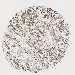

CANCER BREAST CANCER Show tissue menu

BRCA TCGA BRCA VALIDATION PROTEIN EXPRESSION